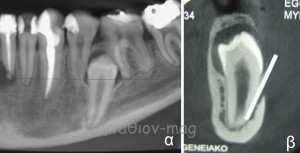

Ωστόσο, στην περίπτωση της εικόνας 2, ο οστικός πόρος έχει πλήρως «αποφραχθεί» από τον έγκλειστο προγόμφιο και το νεύρο απωθούμενο προς τα κάτω τελικά πορεύεται προς το γενειακό τρήμα ανάμεσα στην οδοντική ρίζα και τον εξωτερικό φλοιό της κάτω γνάθου.